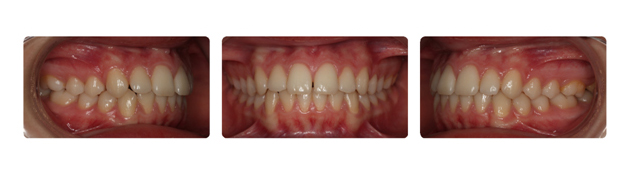

| درمان با براکتهای دیمون نتیجه بخش است: |

| پس از گذشت دو سال از درمان فک و دندانها مرتب شده و سر جای خود قرار گرفته اند: |

| همچنین پس از گذشت یک سال از پایان درمان همچنان نتیجه رضایت بخش است: |